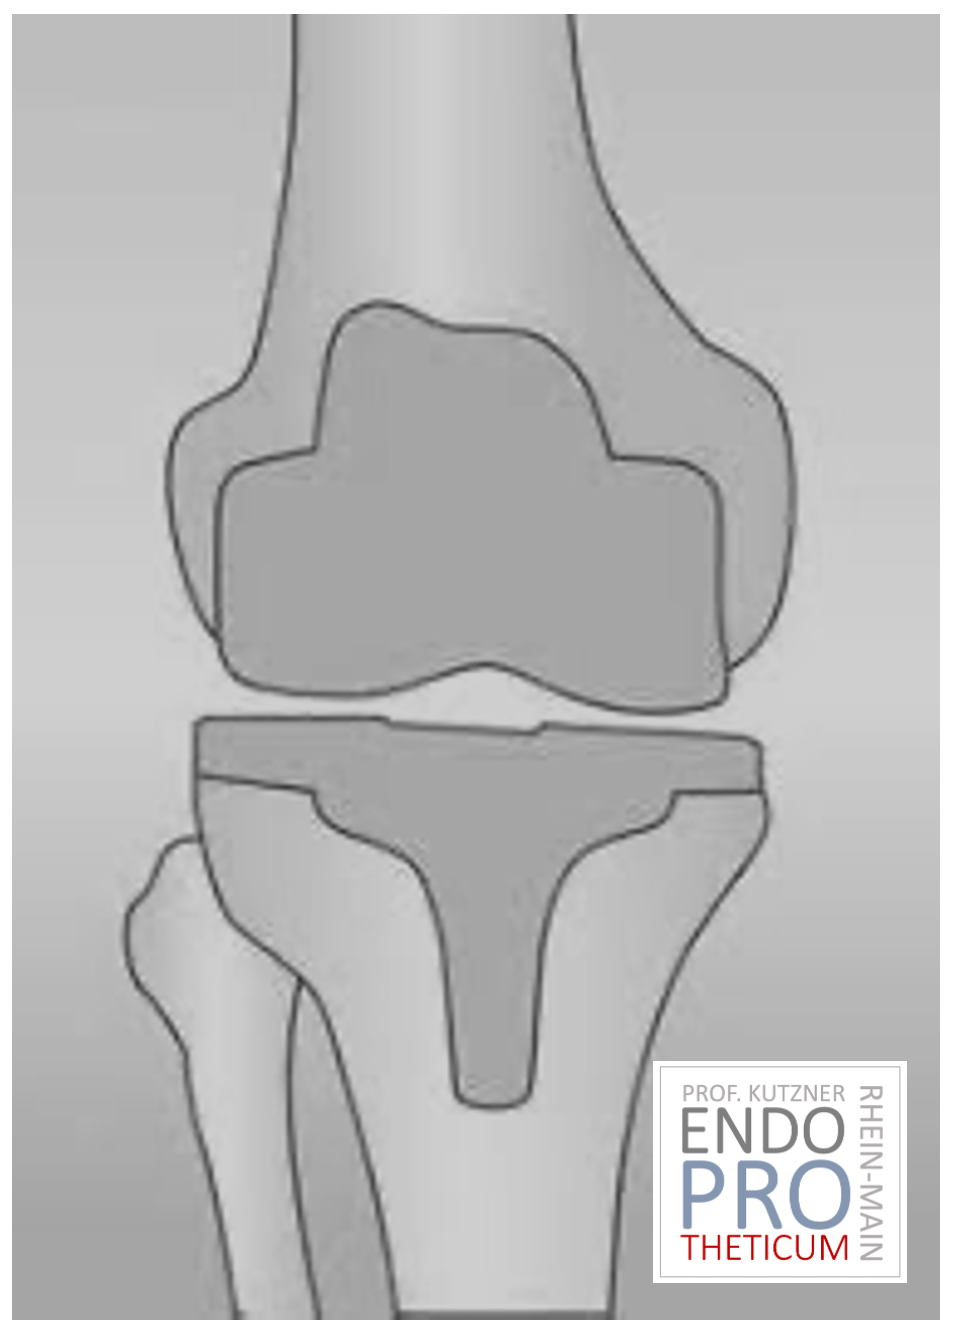

The artificial knee joint replaces the cartilage surface destroyed by arthrosis. The underlying bone on the thigh and tibial head remains intact. Some people compare a modern artificial knee joint to a crown on a tooth; the exact term is the so-called bicondylar surface replacement. Between the new surfaces on the thigh and lower leg is the so-called inlay made of a specially hardened white plastic, which can be seen in the X-ray image as the gap between the metal parts.